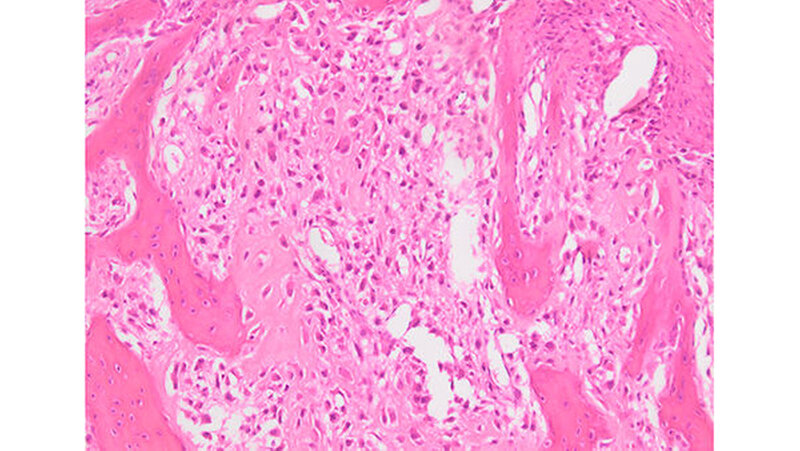

Die endgültige histologische Aufbereitung zeigte einen malignen, Osteoid-produzierenden Tumor, der einem Osteosarkom der TNM-Klassifikation pT2b pN0 (0/37) M0 R0 (Abbildung 8) entsprach. Der postoperative Heilungsverlauf verlief komplikationslos, so dass die Patientin nach drei Wochen nach Anbindung an die Hämatologie in die ambulante Nachsorge entlassen werden konnte. Eine Chemotherapie wurde auf Wunsch der Patientin nicht durchgeführt. Die pulmonalen Verdichtungen erwiesen sich in der Nachkontrolle als größenkonstant. Aktuell ist die Patientin in regelmäßiger Nachsorge ohne Anhalt für ein Rezidiv oder eine Metastasierung.